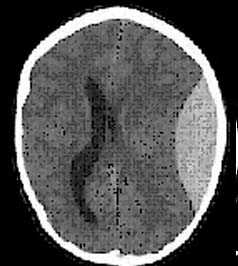

в) Признаки субдуральной гематомы на КТ и МРТ. Субдуральная гематома (СДГ)— скопление крови между твердой мозговой оболочкой и паутинной оболочкой. Чаще всего вызвана разрывом переходных вен (нередко после острых изменений скорости при повреждении паренхимы). Хроническая СДГ может возникать и без травмы или в результате незначительной травмы, особенно у пожилых пациентов.

Ключевые данные визуализации:

- Субдуральная гематома имеет форму полумесяца между костью и мозгом и часто связана с другими поражениями (70%).

- Плотность уменьшается примерно на 1,5 Н/день.

- Может пересекать швы, но не по среднюю линию (не пересекает места прикрепления ТМО).

- Не забыть проверить наличие субдуральной гематомы малого размера у серпа и намета.

- КТ-характеристики гематомы различны в зависимости от продолжительности кровотечения:

— Острейшая СДГ: гетерогенная (40%) или гиперденсная (60%). При гетерогенном варианте гиподенсный сигнал обусловлен ликвором или несвернувшейся кровью (острое кровотечение).

— Острая СДГ (несколько дней): гиперденсная.

— Подострая СДГ (от двух дней до двух недель): изоденсная по отношению к мозгу. При диагностике подострой СДГ необходимо особое внимание, так как ее легко пропустить из-за изоденсного сигнала. Чтобы отличить ее от мозга, необходимо проверить, находится ли серое вещество и борозды в контакте с костью или СМЖ, а граница серого-белого вещества не смещена медиально. В противном случае возможен диагноз подострой СДГ. В случае сомнений внутривенное введение иодинированного контраста поможет определить смещение вен твердой мозговой оболочки и капсулу.

— Хроническая СДГ (от недель до месяцев): может быть однородно гиподенсной, иногда можно увидеть горизонтальную линию, разделяющую гиперденсный объем жидкости (нижний) и гиподенсный (верхний), при хронической СДГ у пациентов при лечении антикоагулянтами или заболеваниями с нарушениями свертываемости крови. Она может выглядеть гетерогенно гипо/изоденсно, с трабекулами и кальцина-тами, а также гетерогенной комбинацией гипо- и гиперденсивных зон при хронической СДГ с рецидивирующим излиянием СМЖ или несвернувшейся крови (острое кровотечение).